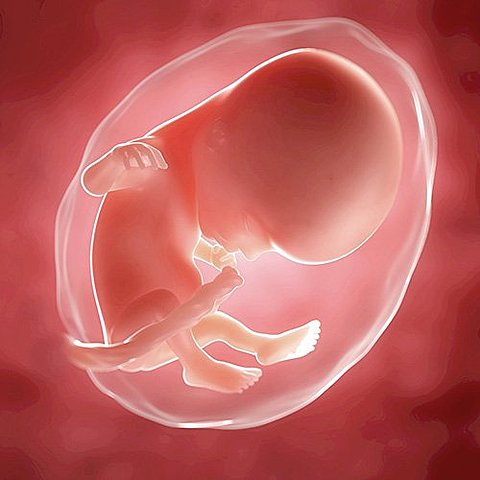

• semana 12

semana 12

La semana 12 de embarazo marca el final del primer trimestre. A las 12 semanas de embarazo, su corazón late muy rápidamente, a unas 160 pulsaciones por minuto o, lo que es lo mismo, el doble de rápido que el latido de la madre. A partir de las 12 semanas de embarazo, tanto el crecimiento y desarrollo del bebé como sus movimientos, todavía imperceptibles para ti, se multiplican exponencialmente.

• semana 13 y 14

semana 13 y 14

A lo largo de estas dos semanas se logra considerar que el feto tienen un aspecto humano. Llas orejas están a su posición definitiva y los delgados párpados se mantendrán cerrados hasta el séptimo mes.